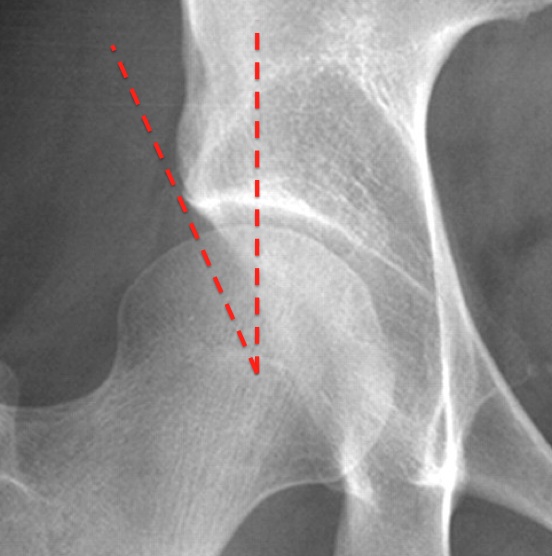

angle formed by a vertical line and a line connecting the femoral head center with the lateral edge of the acetabulum. compare normal (figure 1) with abnormal over coverage (figure 2)

how to draw the center edge angle